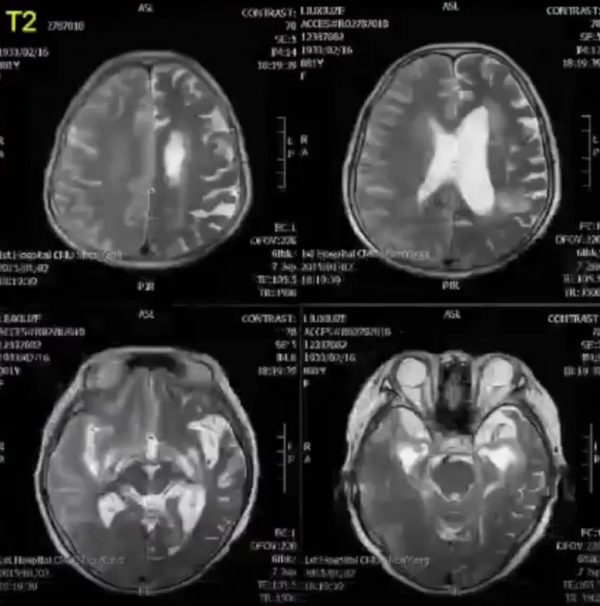

左側大腦半球可見瀰漫性長T1、長T2訊號,腦組織腫脹,腦溝變淺。

左側大腦半球瀰漫性病灶,DWI呈彌散受限高訊號,ADC呈低訊號。

診斷:左側頸內動脈及大腦後動脈供血區腦梗死。